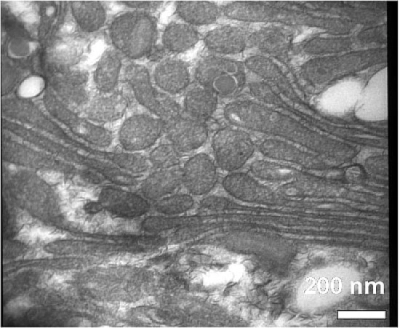

Complexo de golgi e VesÃculas (Embrião...

Complexo de golgi e VesÃculas (Embrião de 47 dias) - 25 חלקים